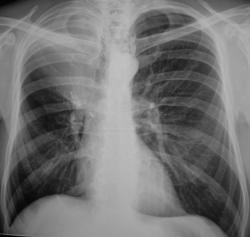

На иллюстрациях 1, 2. Представлены флюорограммы, произведенные в «настоящее время». На флюорограмме, произведенной в прямой стандартной проекции, визуализируется снижение прозрачности легочной ткани верхней доли правого лёгкого однородной структуры, без четких контуров. Правый корень несколько подтянут кверху, что навело на мысль об ателектазе. На боковой флюорограмме дифференцируется снижение прозрачности верхней доли средней интенсивности, однородной структуры с четкими «вогнутыми контурами», имеет место уплотнение структур корня с «кажущейся тяжистостью» кпереди, в средней доле. В грудном отделе позвоночника явления межпозвонкового остеохондроза.